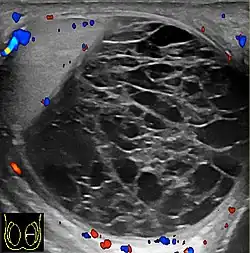

However, these patterns, except the latter one, may be considered as non-specific as heterogeneous echotexture and shadowing calcification can also be detected in malignant testicular tumors. The onion peel pattern of epidermoid cyst [Fig. 10] correlates well with the pathologic finding of multiple layers of keratin debris produced by the lining of the epidermoid cyst. This sonographic appearance should be considered characteristic of an epidermoid cyst and corresponds to the natural evolution of the cyst. Absence of vascular flow is another important feature that is helpful in differentiation of epidermoid cyst from other solid intratesticular lesions.

- An onion peel appearance consisting of alternating rings of hyperechogenicities and

hypoechogenicities.